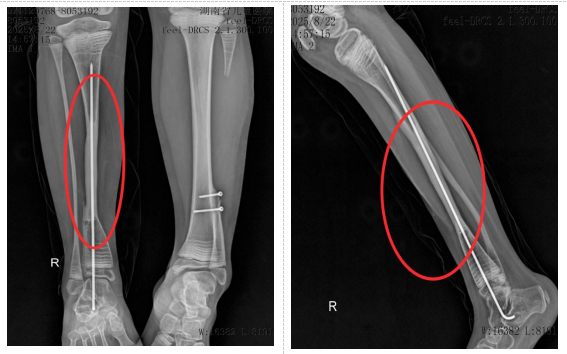

术后两年

经过两年定期复查,影像学检查证实,移植的腓骨已在新的位置“安家落户”,与胫骨牢固愈合,直径明显增粗,具备了良好的承重能力。小小的右下肢长度得到维持,功能恢复良好,生活质量得到了显著改善。